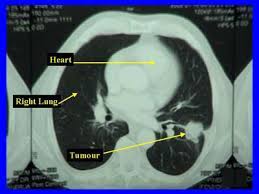

Most lung cancers don't cause symptoms until the disease has advanced, in part because the lungs have few nerve endings. Ct scan showing a cancerous tumor in the left lung. The scan only takes a few minutes and is not painful. Undergoing regular screening may be a good idea for people with a high risk of developing lung cancer. Lung cancer is the leading cause of cancer deaths in males and females in the united states.

Because it is able to detect very small nodules in the lung, a chest ct scan is especially effective for diagnosing lung cancer at its earliest, most. This method of ct scanning builds a detailed image of the body's internal workings. Early detection of lung cancer is being made easier through the use of ct scans. Lung cancer is the leading cause of cancer deaths in males and females in the united states. Around 44,500 people are there are usually no signs or symptoms in the early stages of lung cancer, but many people with if the ct scan shows there might be cancer in the central part of your chest, you'll have a bronchoscopy. This may reveal an obvious mass, the widening of. Most lung cancers don't cause symptoms until the disease has advanced, in part because the lungs have few nerve endings. The scan is painless and takes about 10 to 30 minutes. Ct scan showing a cancerous tumor in the left lung. Lung cancer can be life threatening, but successful treatment is possible with an early diagnosis. Ct scans to find lung cancer in smokers. It is used to look for early signs of lung cancer. Radiological scan is useful in detecting early npc.